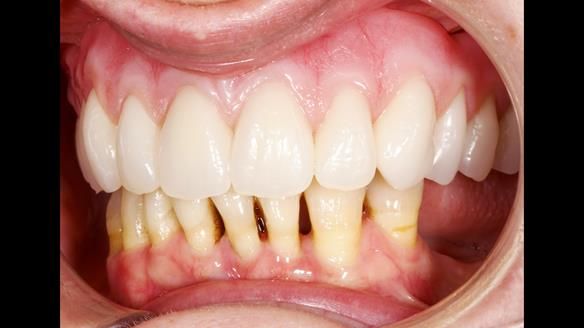

She had previously suffered from generalised periodontitis – stage IV, grade C, currently stable, with reduced attachment across the upper arch.

By the time she came to me, her periodontal condition was stable — but the aesthetics in the upper jaw were very poor.

We provided her with an immediate upper denture (Mk 1), followed by a definitive metal-based upper denture (Mk 2). A lower removable partial denture was discussed, to be made only if needed once the upper treatment was complete. However, at review, this wasn’t necessary — Adnana had excellent neuromuscular control and function, even with a shortened dental arch (SDA).